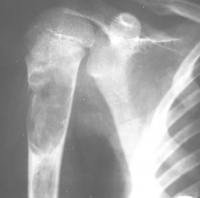

常发生于5到15岁的儿童,男性发病多于女性,比率约为2:1。病变部位多在长骨干骺端。最常见部位为肱骨近端,其次为股骨近端。活动性(active相对具有侵袭性的)骨囊肿靠近骨骺区,随着儿童年龄增大,病灶会逐渐远离骨骺,成为非活动性(inactive)。在年龄超过17岁的患者,病变会在非长管骨发生,如跟骨骨盆等。

1.好发于4-20岁,多见于5-15岁儿童,少见于成人。好发于股骨颈、股骨上端和肱骨上端。随着年龄增长,囊肿逐渐向骨干方向移动。

X线表现病损为界限清楚的射线透亮区,外有一薄层骨硬化边缘,由于囊肿膨胀性生长,造成骨皮质不规则变薄,X线片常呈假分叶状表现,尤多做囊肿在肱骨或股骨的干骺端向下扩展至骨干,向上扩展虽接近骨骺,但后者可被累及,病理性骨折很常见,囊肿可有骨嵴假象,病理检查见病损为单房的囊腔,其中充满清液,囊内衬以薄层纤维组织,骨折后腔内含血性液体并出现骨痂。

X线平片位于长骨干骺端,呈圆形、卵圆形或柱形,沿长骨纵轴发展,表现为轻度膨胀性生长,局部骨皮质变薄,边缘光整,无骨膜增生。合并病理骨折时,骨碎片向囊内移位,称“碎片陷落征”,有助于鉴别。